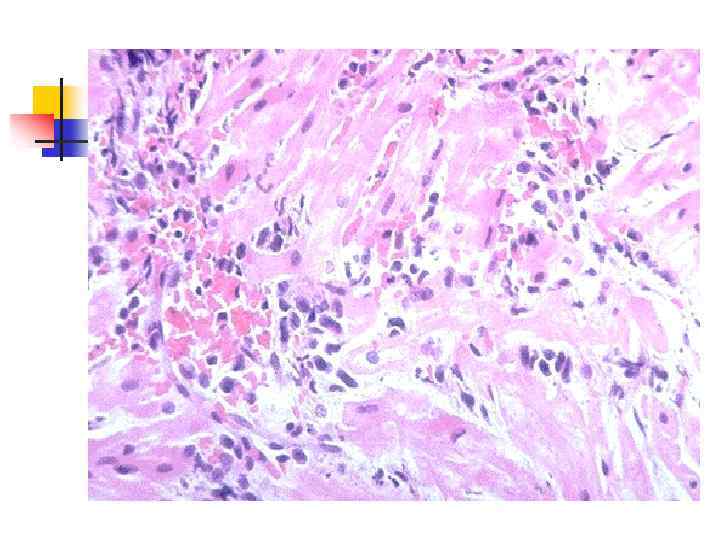

Общие изменения n n n дистрофические; воспалительные; гиперпластические. Дистрофические процессы возникают в паренхиматозных органах (печень, почки, миокард, мышцы, ЦНС) и проявляются различными изменениями: от мутного набухания до некроза. Воспалительные изменения носят характер межуточных процессов, выражающихся межуточным отеком, лимфоидной и лейкоцитарной инфильтрацией - межуточный септический нефрит, миокардит, гепатит и т. д. На клапанах сердца может возникать острый язвенный тромбоэндокардит с расплавлением ткани клапанов и их отрывом. В стенке сосудов также возникают воспалительные изменения (васкулиты). На почве изменений сосудов появляются кровоизлияния.

n n Септический или бактериальный эндокардит (sepsis lenta) обычно вызывается белым и золотистым стафилококком, зеленящим стрептококком (преимущественно L- формы и мутанты), реже гемолитическим стрептококком, пневмококком, энтерококком, кишечной и синегнойной палочками. Септический эндокардит является результатом гиперергии, по сути септицемией с септическим очагом на клапанах сердца (чаще аортальных). В основе гиперергии лежат реакции гиперчувствительности, обусловленные воздействием циркулирующих в крови токсических иммунных комплексов, которые содержат антиген возбудителя. С циркуляцией в крови иммунных комплексов связаны такие проявления септического эндокардита как генерализованные васкулиты, резкое повышение сосудистой проницаемости, тромбоэмболический синдром, клеточные реакции стромы и др.